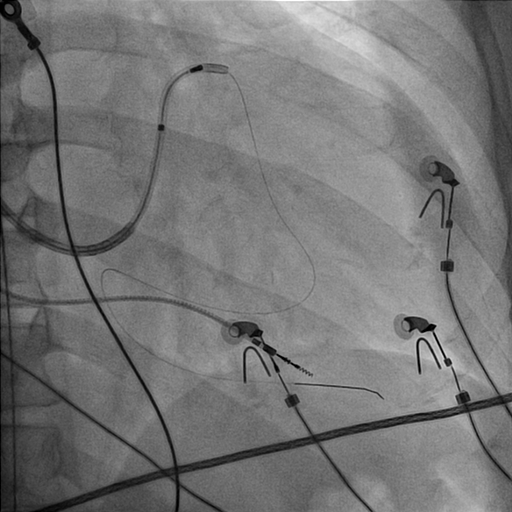

Left bundle lead in place

LB_lead.jpg

Final position

final_position.jpg